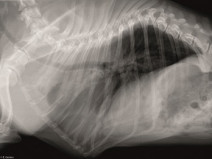

• Les boiteries du jeune

La section Sud-Est vous propose une journée de formation en pathologie orthopédique chez le jeune animal. A l'issue de cette formation, le participant devra être capable de réaliser un cliché radiographique de qualité et l'interpréter et de prendre en charge une affection du cartilage chez le jeune.